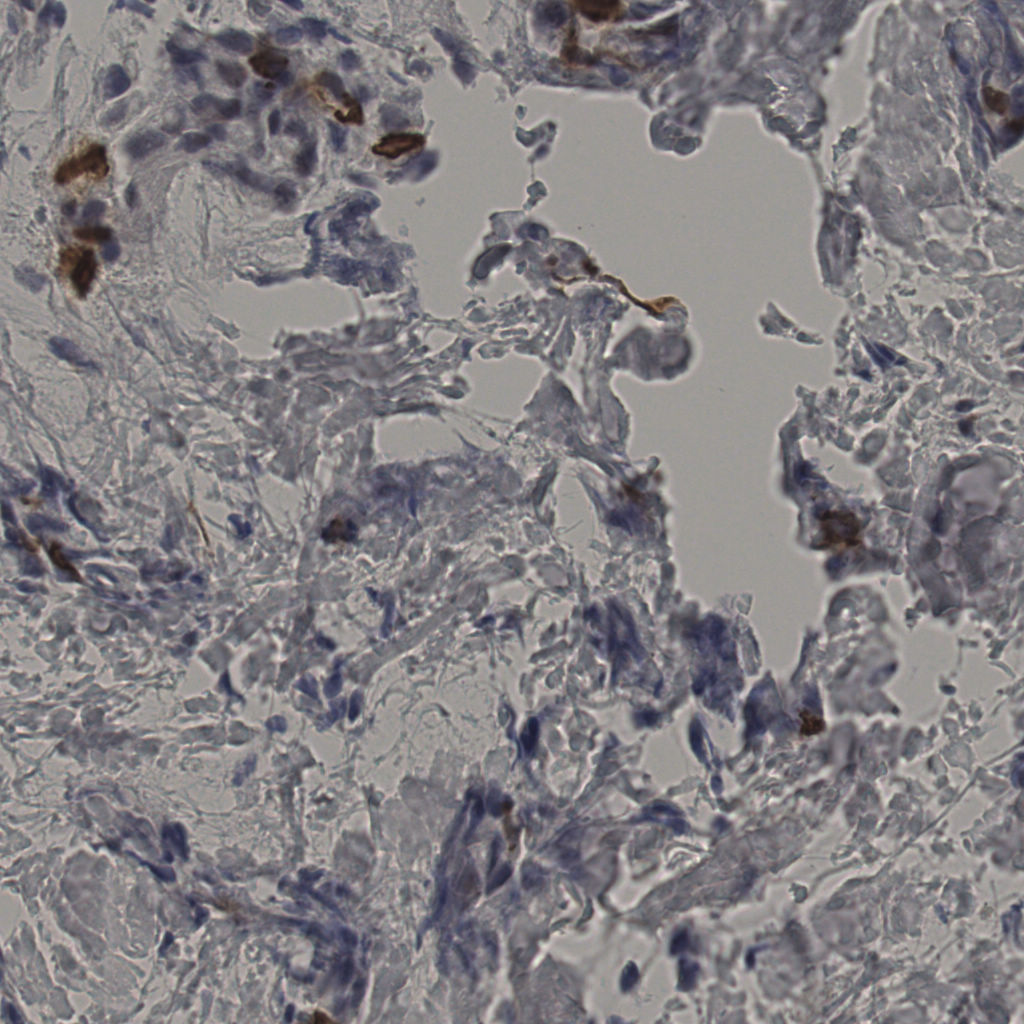

缩略图

标记后

标记前